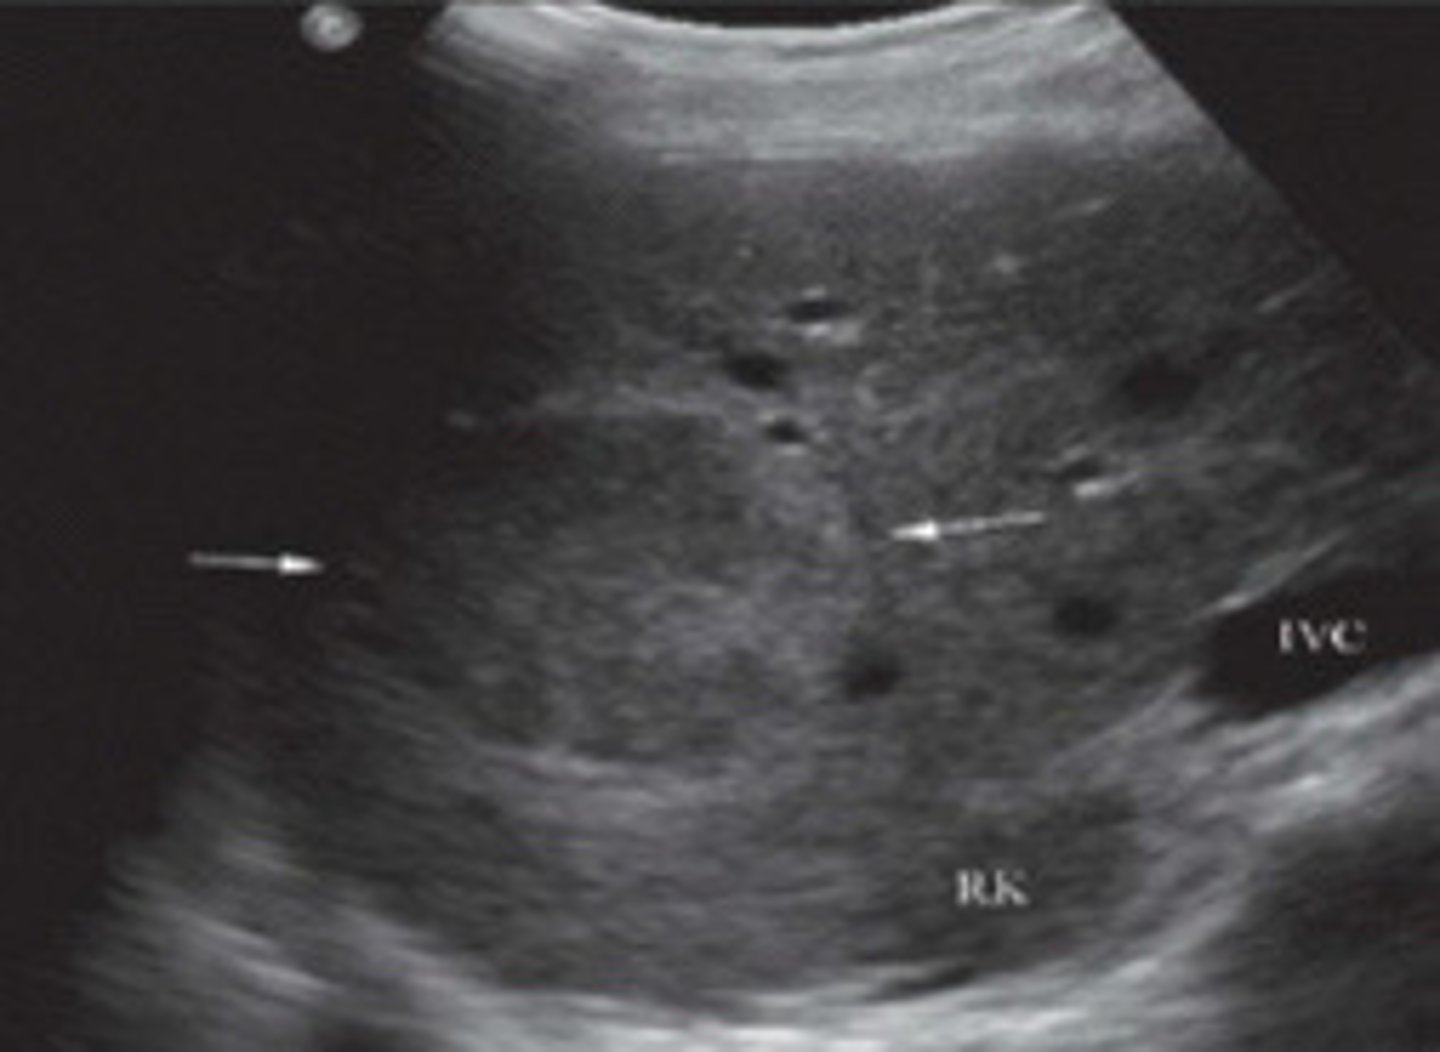

FNH

What does this image show

FNH (seen better with colour map)

What are the arrows pointing to